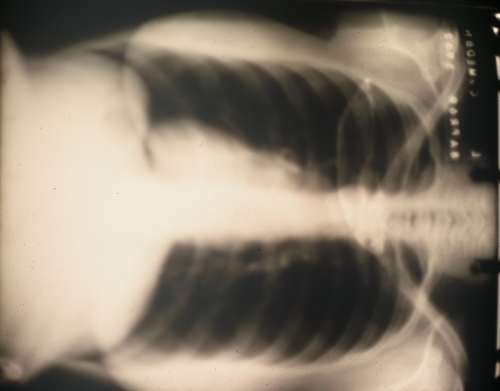

15) The airstrip with the evening monsoons coming in.